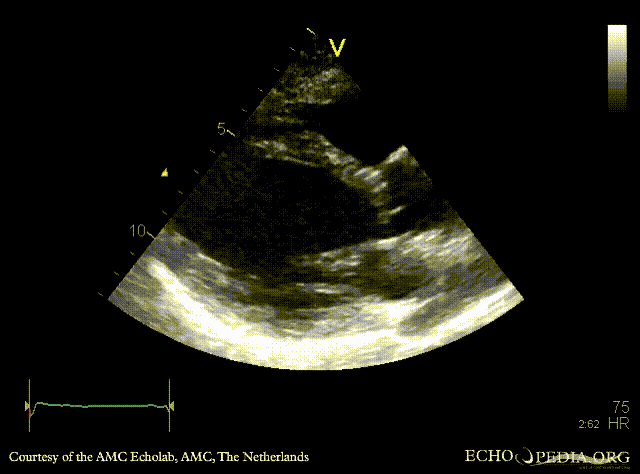

E00707.gif E00708.gif

A4CH: dilated left ventricle, poor function, akinesia of inferoseptal wall A2CH: dilated left ventricle, poor function, akinesia of inferior wall